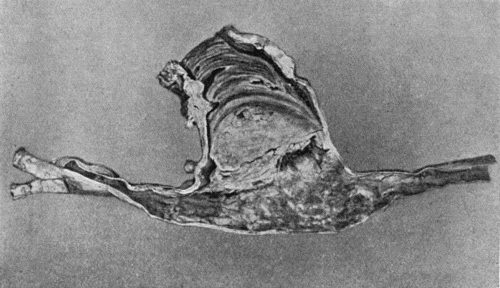

109.Volkmann's Ischæmic Contracture 414